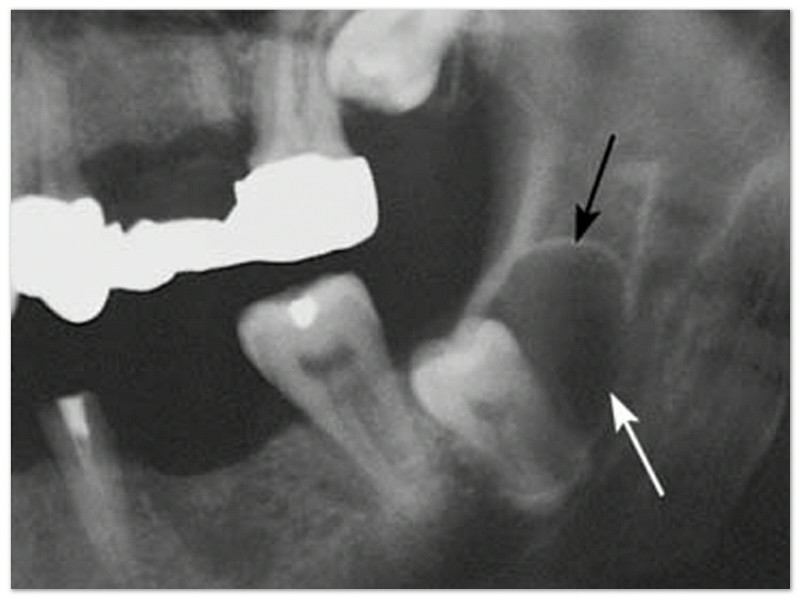

Gigi bungsu sering tumbuh dengan arah miring ke depan, sehingga mendorong gigi-gigi di depannya dan membuat gigi di depannya menjadi berantakan. Oleh karena itu, apabila ingin menggunakan kawat gigi, dokter gigi sering menganjurkan pengambilan gigi bungsu yang menjadi penyebab gigi berantakan.

Merusak akar gigi sebelahnya.

Selain menyebabkan gigi berantakan, gigi bungsu yang arah tumbuhnya ke depan juga dapat menyebabkan gigi di sebelahnya menjadi rusak.

Selain gigi bungsunya tidak tumbuh, gigi disebelahnya juga bisa ikut terbenam.